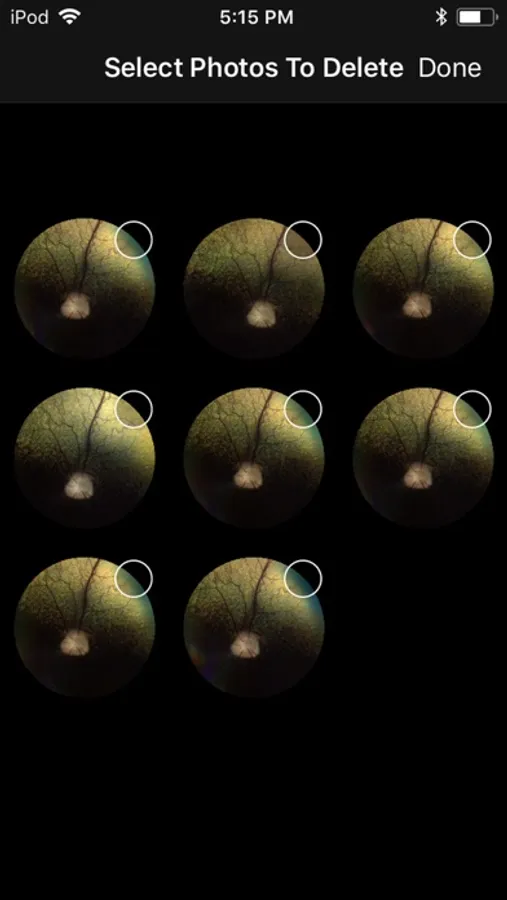

Award winning veterinary retinal imaging app for use with the Optibrand ClearView2 retinal imaging attachment. Using an iPhone or iPod Touch and a Optibrand ClearView2 retinal imaging attachment gives veterinarians and veterinary ophthalmologists an affordable and easy to use method for obtaining retinal images for purposes of disease diagnosis, general visualization, owner education, and record retention. ClearView2 uses patented auto capture technology that eliminates the need for operators to manually capture images.

ClearView2 Screenshots

Screenshot 1Screenshot 2Screenshot 3